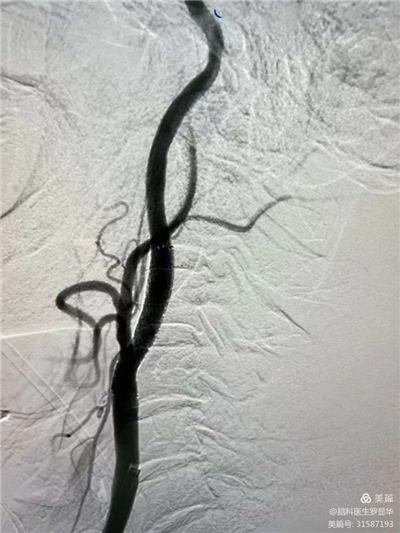

李東波副院長團(tuán)隊正在為患者行頸動脈支架植入術(shù)

手術(shù)過程:指引導(dǎo)管到位

手術(shù)過程:球囊擴(kuò)張后,protege支架到位

術(shù)后造影示狹窄解除